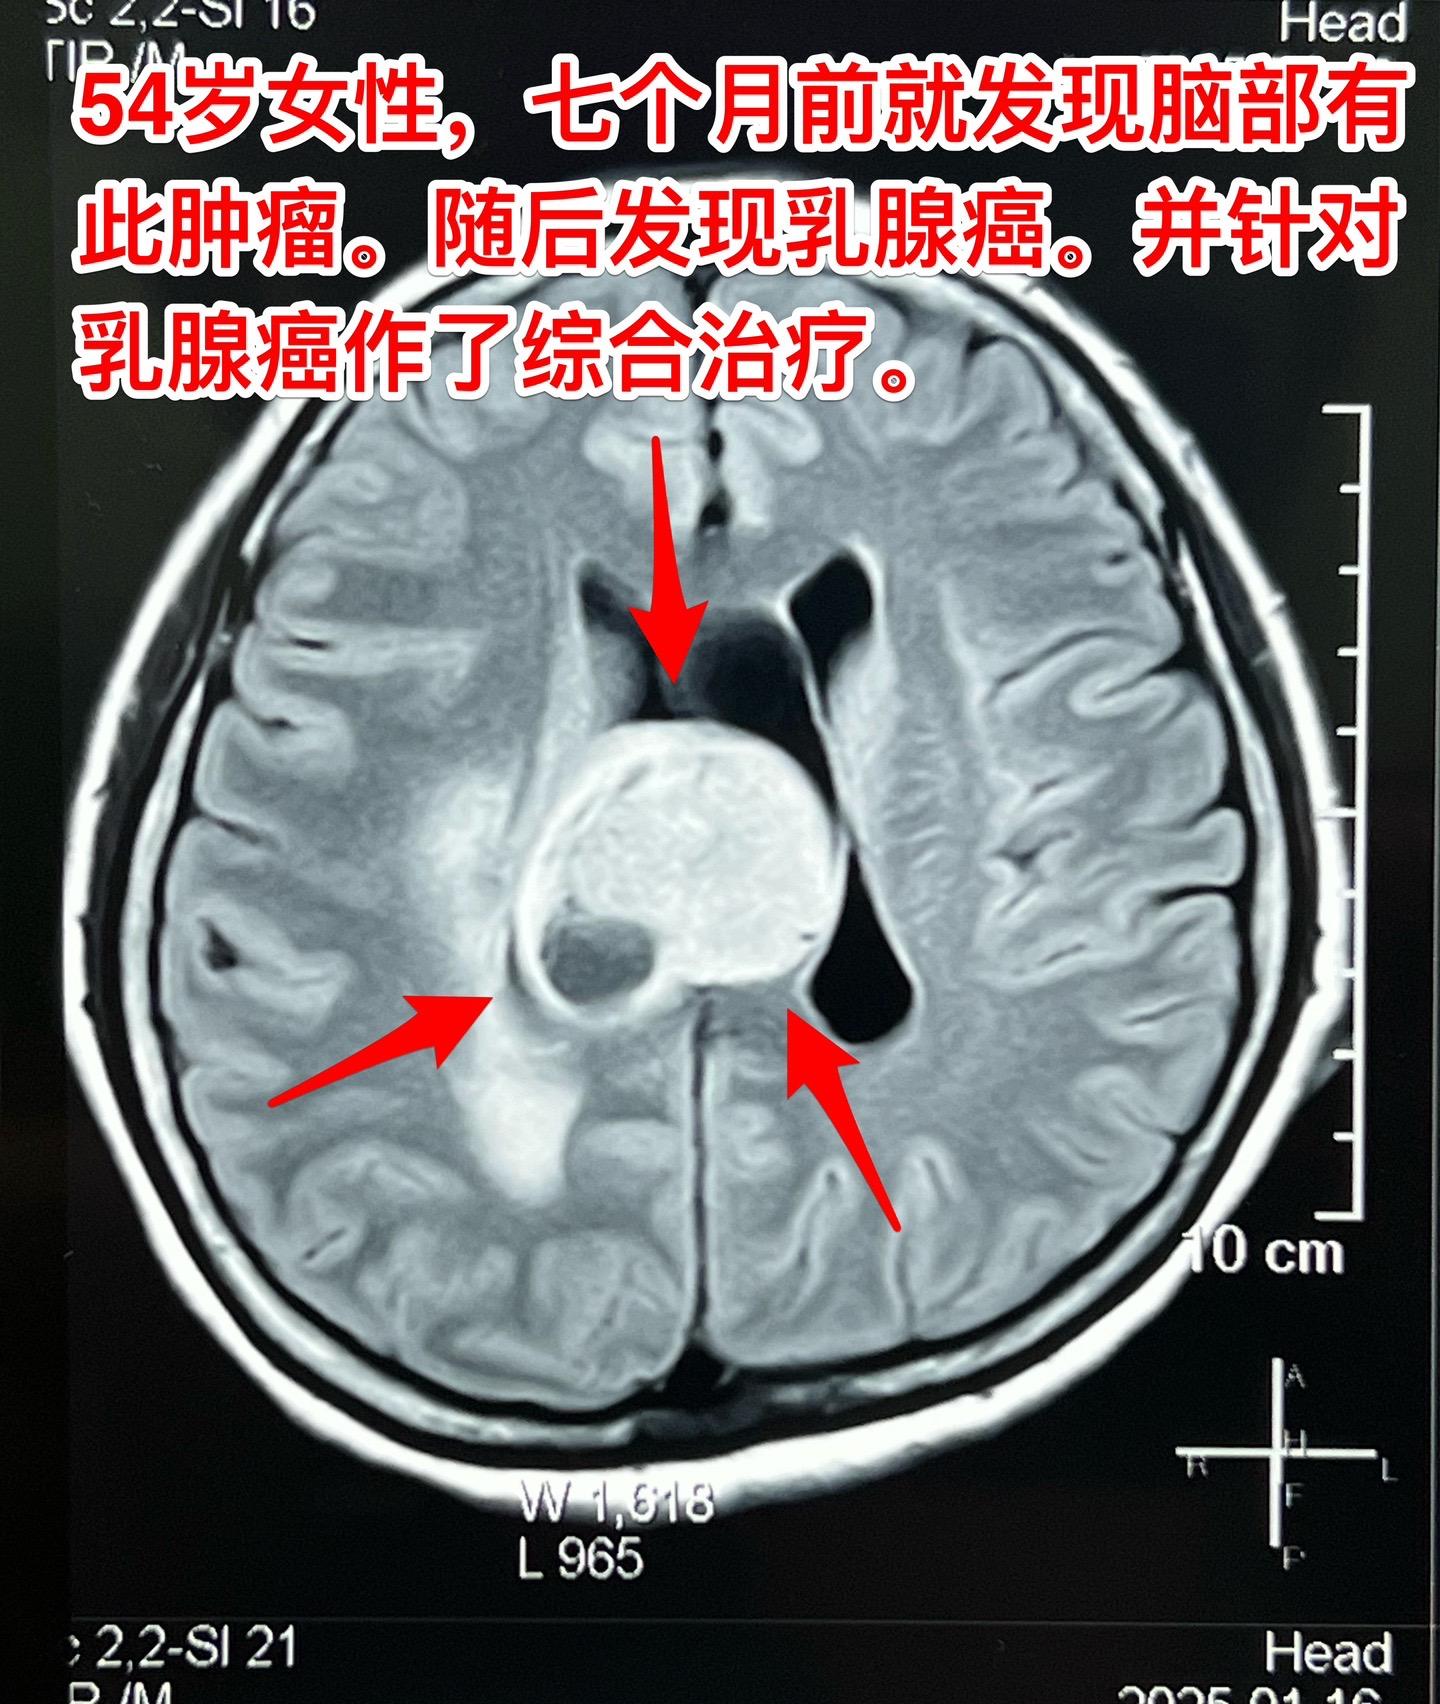

乳腺癌也能转移到脑部。脑部的转移瘤约80%来源于肺癌,绝大多数是腺癌。...